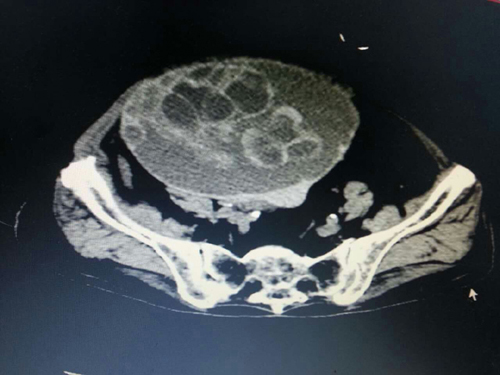

羅奶奶,衡南縣人,98歲高齡,平時跟兒子居住在桂林,2016年1月10日突發(fā)劇烈腹痛,在當?shù)蒯t(yī)院就診,確診為“腹腔巨大腫瘤”,急需手術治療,但因羅奶奶年事已高,耐受手術能力差,手術風險高,桂林多家大醫(yī)院均拒絕收治。羅奶奶兒子焦急萬分,通過家鄉(xiāng)親戚介紹,慕名前來我院肝膽外科。患者入院后經急診CT檢查示:腹腔有一大小15.×16×18cm巨大腫瘤,腫瘤已經扭轉,開始破裂出血,病情十分危重,羅奶奶危在旦夕,只有急診手術才有一絲希望??粗颊咄纯嗟拿嫒?、家屬期盼的目光,手術做還是不做?如何去做?如果不做手術,患者隨時有生命危險;如果做,年邁體弱的患者能否承受麻醉以及手術的打擊,能否安全度過圍手術期,疾病能否得到根治?“醫(yī)者仁心,我無法拒患者于門外,并且我相信我們的科室、我們的團隊、我們的醫(yī)院有這個能力完成這個高難度的手術!”肝膽外科主任李珍發(fā)如是說。經過精心、細致、周密的圍手術期準備后,李珍發(fā)主任、副主任醫(yī)師蔣水平帶領科室手術團隊,在麻醉科主任段雪琴的密切配合下,成功為患者摘除重達10余斤的腹部巨大腫瘤。術后,在許敏護士長帶領的護理團隊精心護理下,羅奶奶恢復順利,能下床自由活動,未出現(xiàn)任何并發(fā)癥,10日后痊愈出院。出院時,羅奶奶及全家感激不已,特向科室送來感謝信和錦旗。